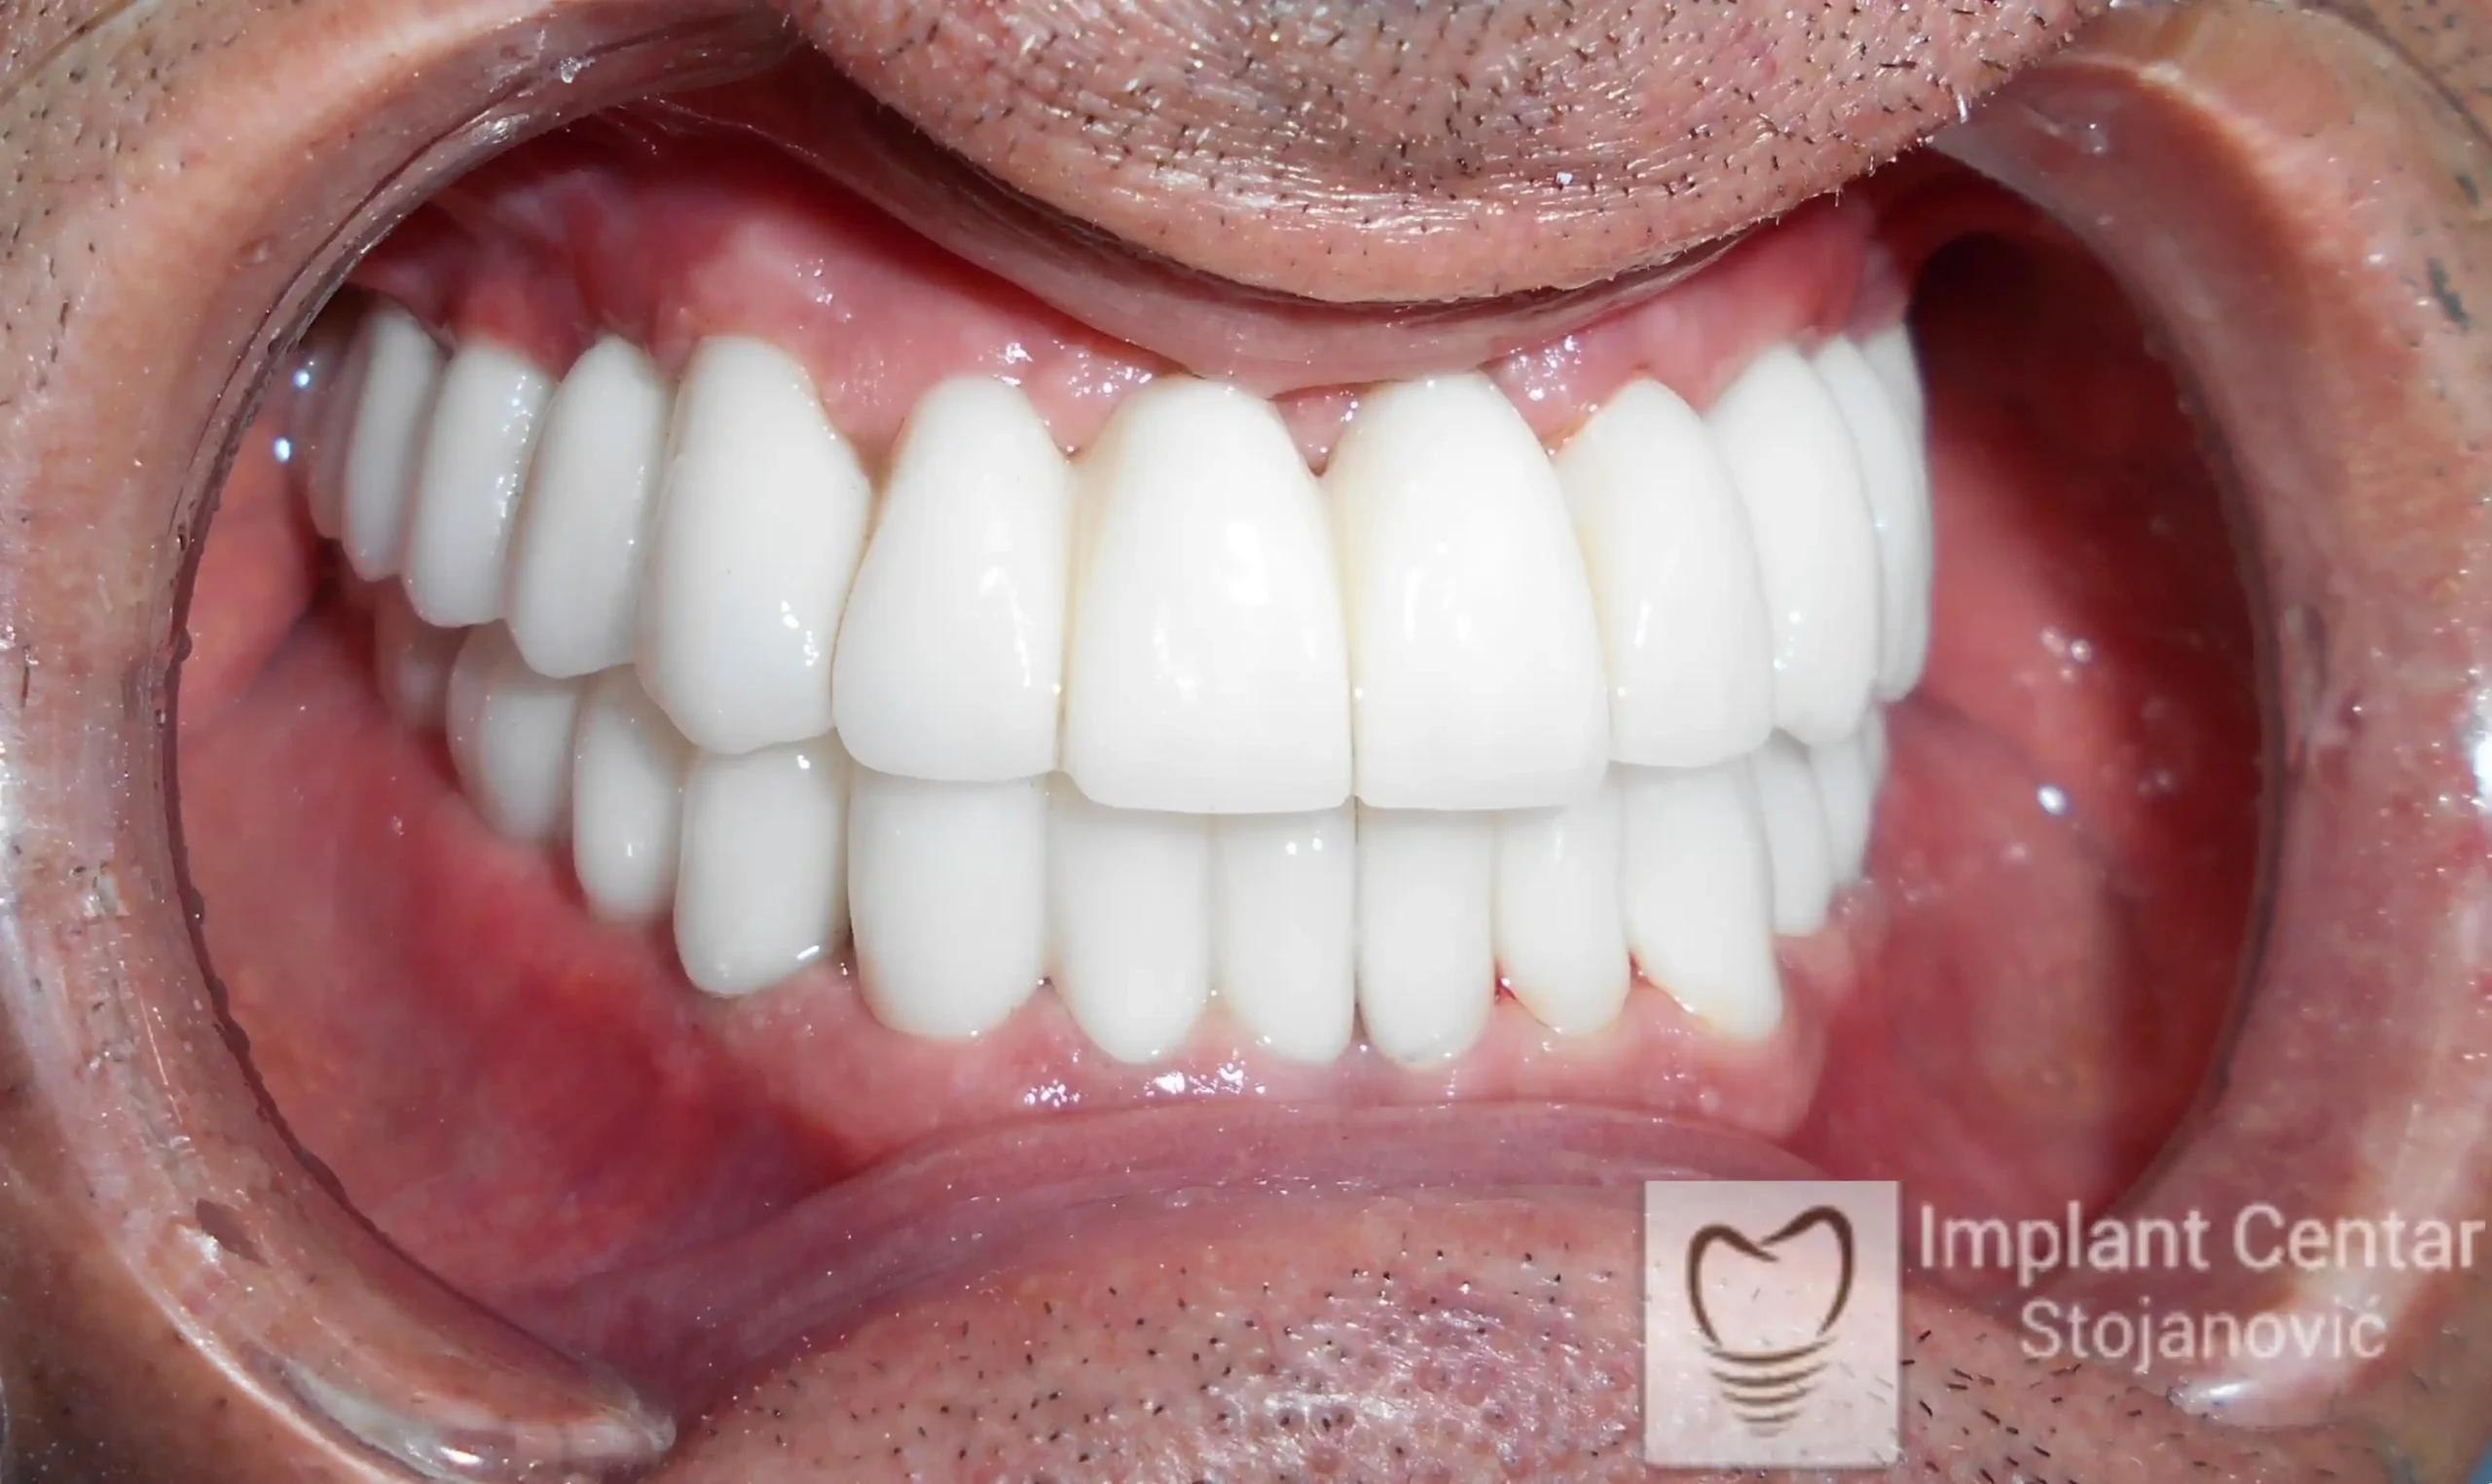

Na slikama 5. i 6. prikazan je izgled definitivnih cirkonijum-keramičkih mostova na implantatima.

Pacijent je izuzetno zadovoljan — kako estetikom novog osmeha, tako i funkcijom, jer ponovo može bez problema da jede i da se smeje.